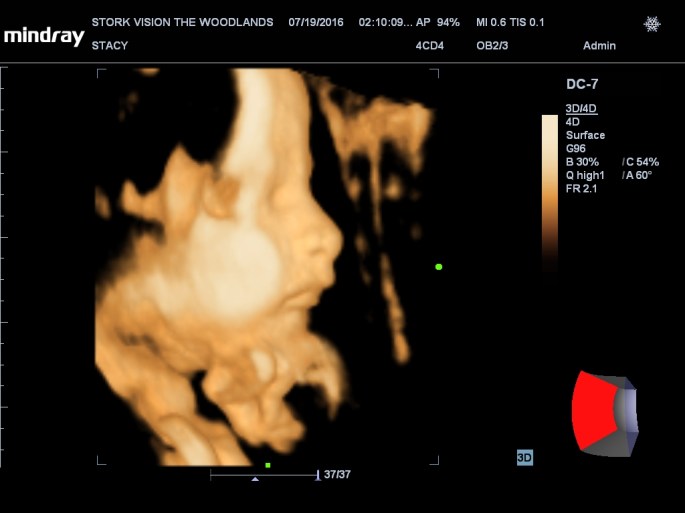

Best moment the week: Seeing Juliette on the 3D/4D ultrasound. So amazing!